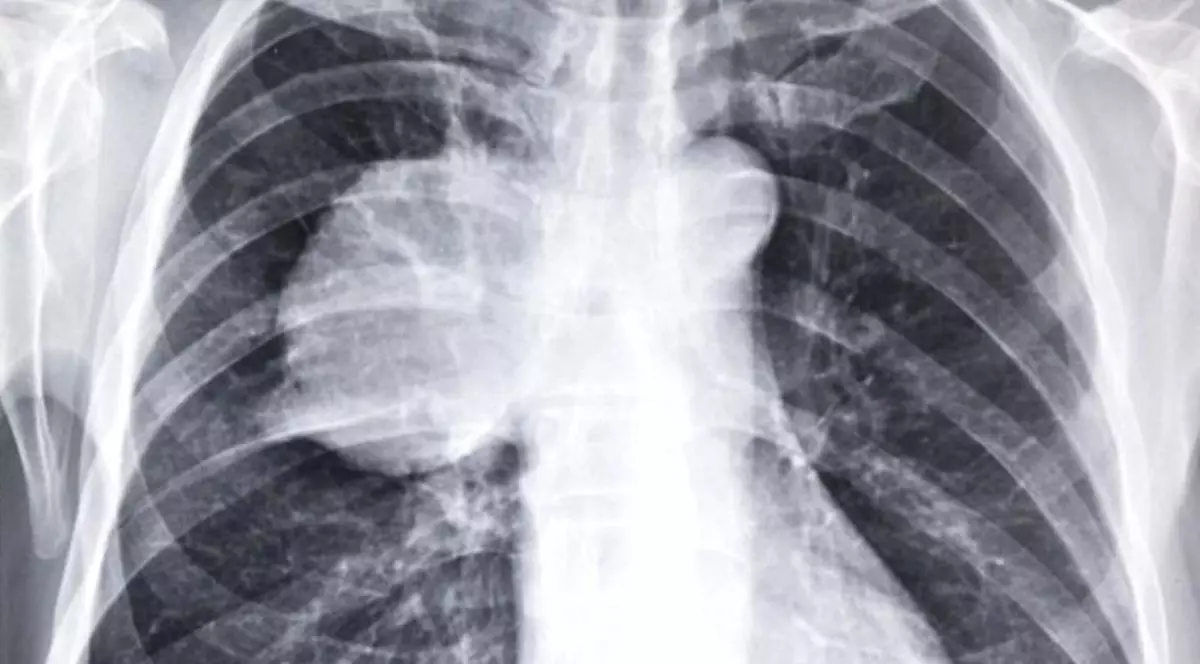

Pneumonia este o infecție respiratorie acută ce poate fi cauzată de bacterii și virusuri. Plămânii celor afectați se umplu cu puroi şi lichid, ceea ce face respiraţia greoaie și dureroasă.